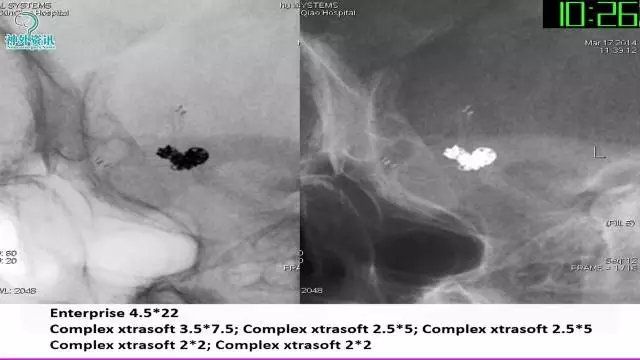

今天为大家分享的是“强生医疗CNV-神经介入专栏”第三十六期,由重庆第三军医大学附属新桥医院神经外科刘俊带来的“Galaxy弹簧圈在不规则动脉瘤中的临床应用”精彩讲课视频及PPT,欢迎观看。文章仅代表作者个人观点,如有不同见解,欢迎同道斧正!